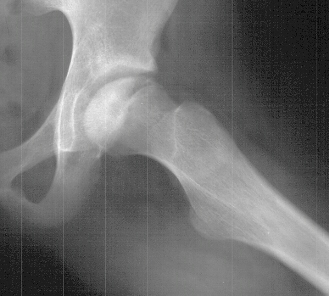

Salmonella

is the most common infectious organism in osteomyelitis in individuals

with sickle cell disease.

Children

in mid-childhood with sickle cell disease develop avascular necrosis

of the femoral head which responds similar to Perthes disease

of the hip.